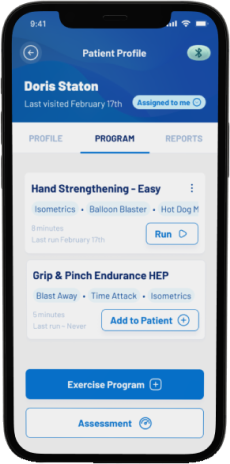

Grip/ Pinch Assessment And Data Tracking

Smart Dynamometer and Hand Trainer

Medical device and a connected app solution for grip/pinch strength assessment, monitoring and training.